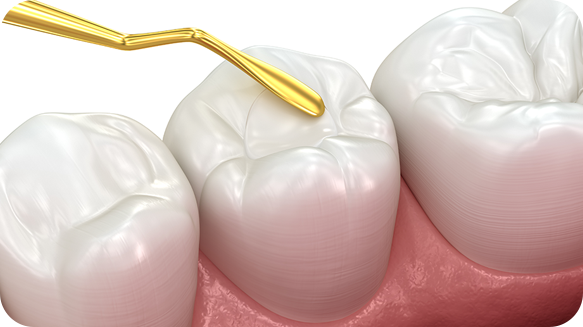

신경치료는 자연치아를 살리는 방법입니다.

신경치료는 충치나 외상 등으로 인해 치아 신경이 자가 치유되지 않거나 괴사되었을 때 시행하는 치료입니다. 치아를 보존해 제 기능을 할 수 있도록

신경 조직을 완전히 제거하고, 대체 약물을 채워 넣는 정교하고 난이도 높은 치료법입니다.

신경치료 진행 단계

신경치료는 치아에 구멍을 뚫어 신경을 제거한 후 특수 물질을 채워넣는 시술로 매우 정밀한 치료입니다.